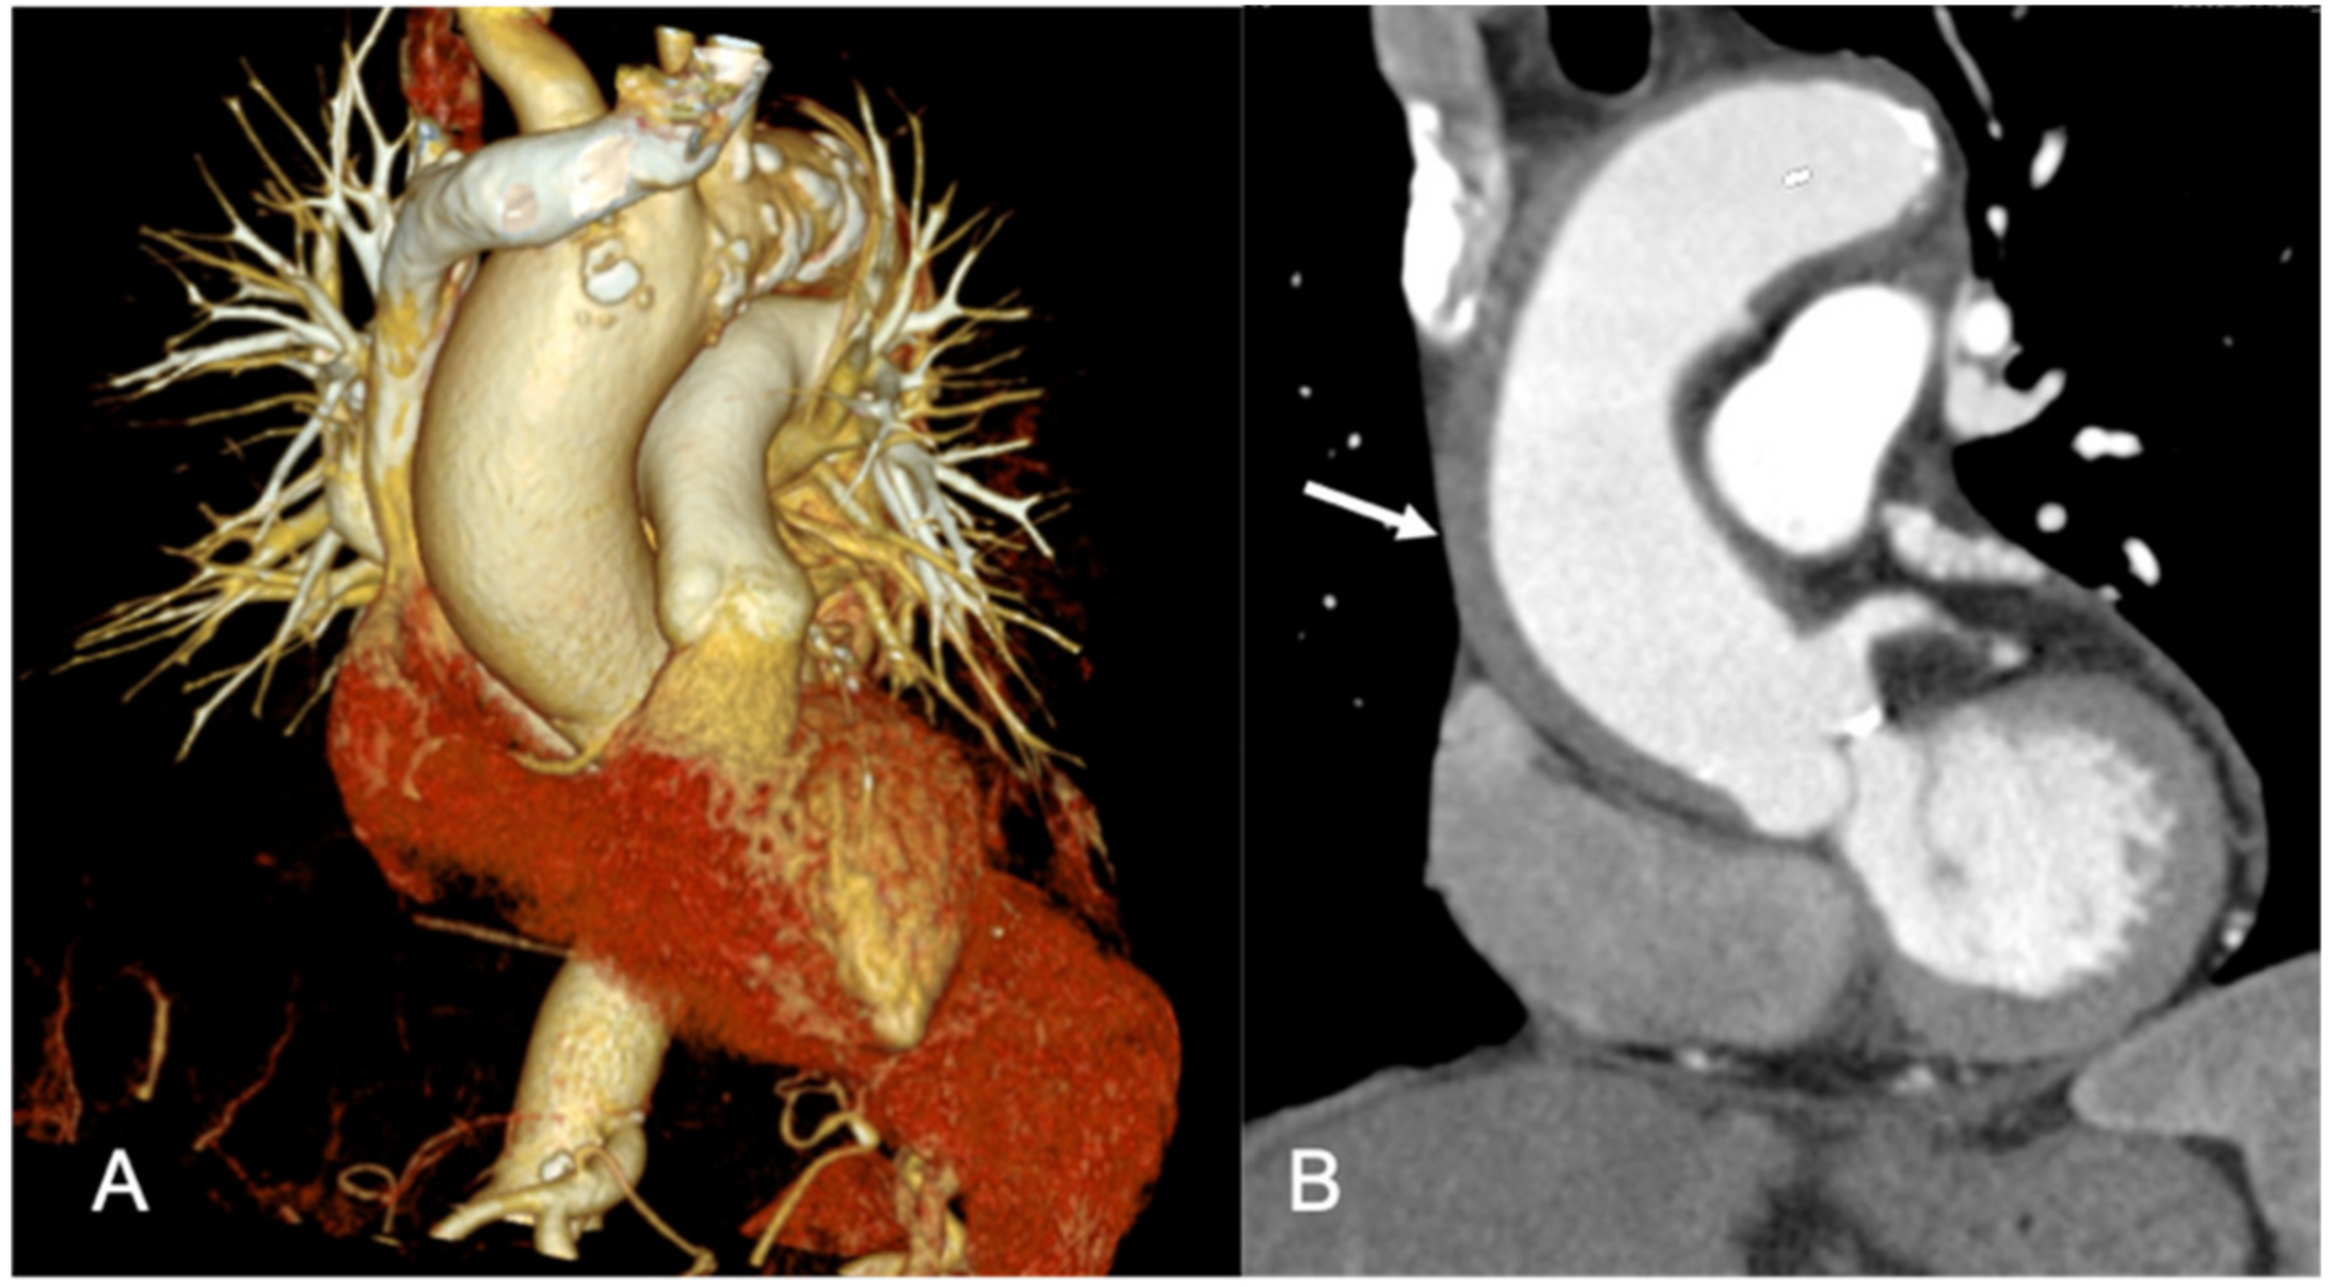

1.1. Computed Tomography and Magnetic Resonance Imaging Benefits

1.2. Role of Coronary CT